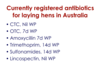

* Heavy metal toxicity, mycotoxins (ochratoxicosis), medications (aminoglycosides, sulphonamides), excess dietary calcium (young chickens), hypervitaminosis D (also through hypercalcaemia)